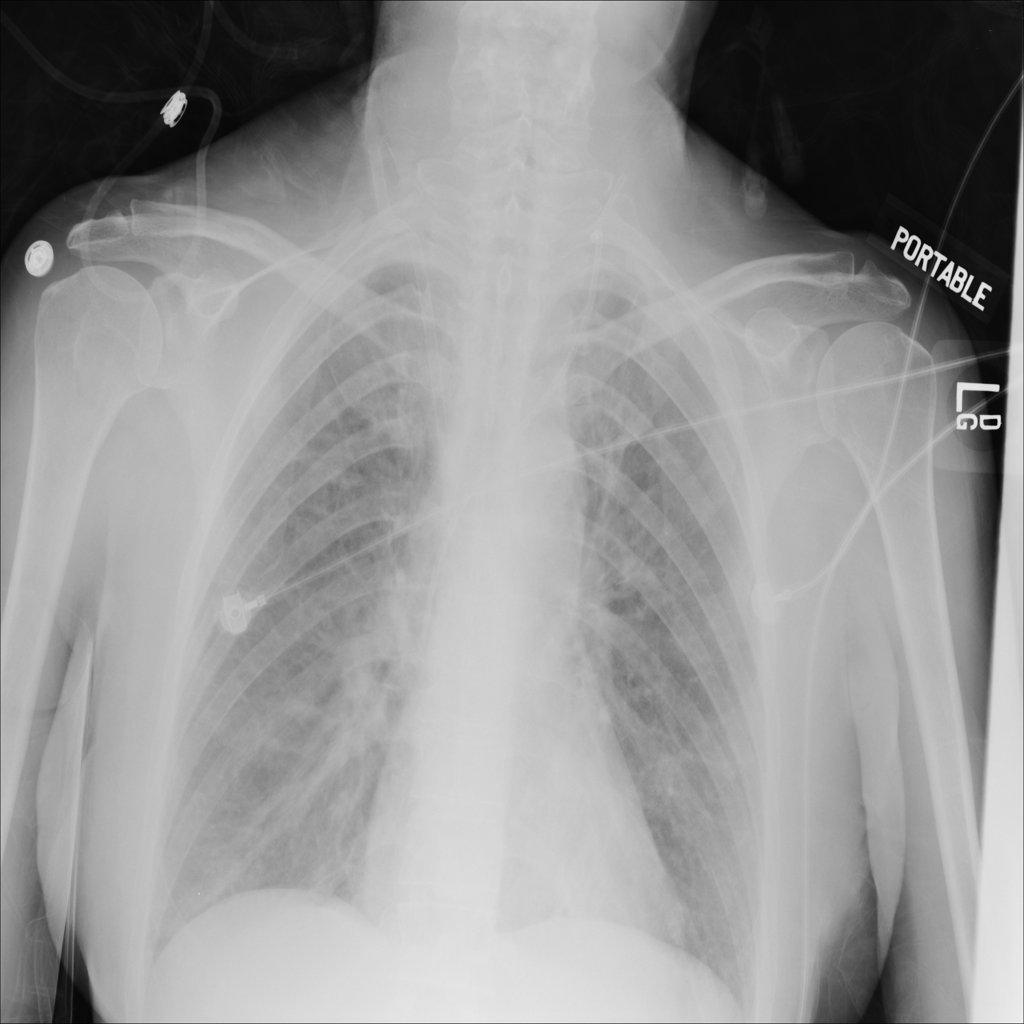

PAT-E828 · IMG-004Edema

PAT-E828 · IMG-004

AP